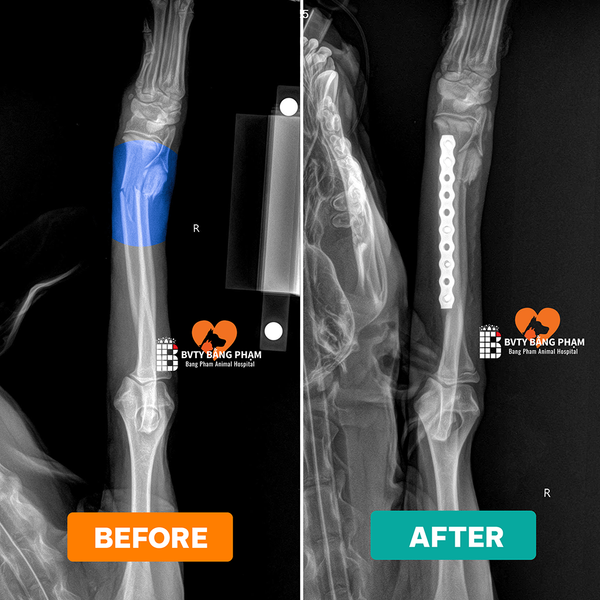

- Khi cần lập kế hoạch phẫu thuật hoặc đánh giá trước và sau điều trị – CT cung cấp ảnh 3D và thông tin rõ nét về vị trí, kích thước và mối quan hệ của tổn thương.

🔍7. Hình Ảnh Thực Tế – Kết Quả Sau Khi Chụp

Hình ảnh CT thể hiện chi tiết từng lớp cấu trúc trong cơ thể, giúp bác sĩ:

- Xác định chính xác vị trí khối u, ổ áp xe, hoặc chấn thương sâu.

- Lên kế hoạch phẫu thuật hoặc điều trị nội khoa chính xác.